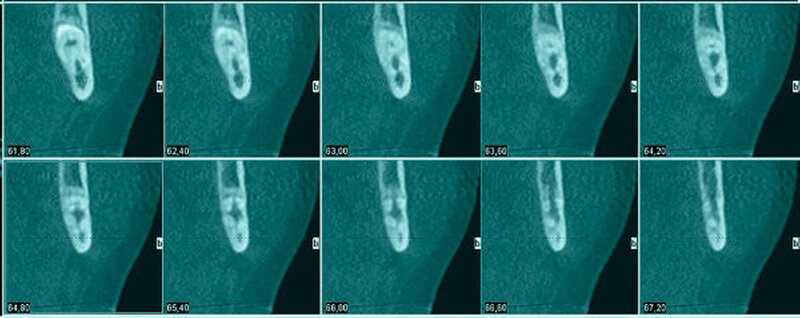

Aufgrund der engen Lagebeziehung der Weisheitszähne zum Nervus alveolaris der jeweiligen Seite wurde zur weiterführenden Diagnostik eine digitale Volumentomografie durchgeführt.

In der 3-D-Aufnahme bestätigte sich der Verdacht, dass der Nerv zwischen den Wurzeln hindurch zog, wobei beim Zahn 48 die Wurzeln den Nerv komplett umklammerten (Abbildungen 3 und 4). Nach Inzision auf dem aufsteigenden Unterkieferast mit Entlastung an den Zähnen 37 beziehungsweise 47 wurden der Knochen und im Weiteren die Weisheitszähne dargestellt. Die Kronen wurden von der Wurzel getrennt, die Wurzeln separiert und sukzessive entfernt, wobei die Integrität der Nerven auf beiden Seiten erhalten blieb (Abbildung 5).

Eine Verletzung des Nervus alveolaris inferior bei Weisheitszahnentfernung findet sich überproportional häufig in Fällen, in denen auf der Panoramaschichtaufnahme Zeichen zu erkennen sind, wie eine Veränderung des Verlaufes des Nervus alveolaris inferior (Abbildungen 1 und 2), bei überlagerungsbedingter erhöhter Transluzenz im Bereich der Überprojektion von Wurzel und Nerv und bei Unterbrechung der kortikalen Begrenzung des Nervkanals [Blaeser et al., 2003]. Alle diese Kriterien lagen im vorliegenden Fall vor. In der weiterführenden digitalen Volumentomografie ist zu erkennen, wie der Nerv zwischen den Wurzeln liegend hindurchzieht.

Man kann den Nerv-Verlauf im DVT besser beurteilen als in der Panoramaschichtaufnahme.